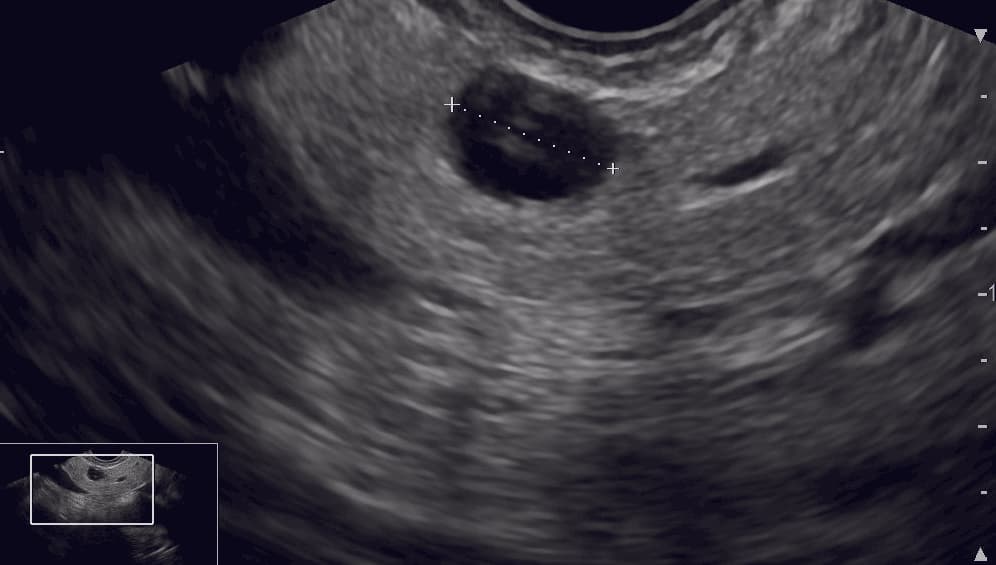

Introduction: With the increasing use of cross-sectional imaging, the incidence of non-symptomatic pancreatic cystic neoplasms is increasing. Surgical management of pancreatic cystic neoplasms possess significant risks of perioperative morbidity and mortality. Our aim was to evaluate endoscopic ultrasound (EUS)-guided ablation as a non-operative treatment of pancreatic cystic neoplasms.

With the increased use of cross-sectional imaging, non-symptomatic pancreatic cystic neoplasms (PCN) are identified in 2.4-13.5% of the adult population [1-3]. PCN include benign lesions such as serous cystic neoplasms (SCN) and pancreatic pseudocysts as well as cystic lesions with malignant potential such as mucinous cystic neoplasms (MCN) and intraductal papillary mucinous neoplasms (IPMN) [4-6]. Surgical management of PCN is associated with significant risks of perioperative morbidity (20-50%) and mortality (2-3%) [7-9]. Current guidelines agree that absolute indications for surgical resection are MCN with a cyst diameter > 40 mm, main-duct IPMN with a pancreatic duct diameter > 10 mm and branch-duct IPMN with a cytology with high-grade dysplasia or presents mural nodules > 5 mm [10, 11]. However, it is challenging to decide on whether to initiate surveillance or perform surgery on patients with pancreatic cysts with limited potential for malignant transformation and in patients who are poor surgical candidate patients. These patients are frequently offered surveillance with either MRI or endoscopic ultrasound (EUS) [10, 11]. Numerous studies have investigated the possibilities of endoscopic ultrasound-guided pancreatic cyst ablation (EUS-PCA) as a minimally invasive alternative to surgery for patients diagnosed with PCN. The purpose of this review was to provide an overview of the various types of ablative agents used in patients with pancreatic cystic lesions and to evaluate EUS-PCA as a possible non-operative treatment of PCN, thus assessing the rate of complete resolutions in ablated cysts, the risk of adverse events as well as the predictors for complete resolution.

For years, the diagnosis of pancreatic cystic lesions has been debated vividly. Different criteria for diagnosing cyst types were applied in the studies included in this paper. Current guidelines agree that EUS is recommended as an adjunct to MRI and CT when the cyst type is uncertain. Also, EUS can be helpful in identifying mural nodules [33, 34]. EUS fine-needle aspiration and cyst fluid analysis improve the diagnostic accuracy for differentiation between mucinous and non-mucinous cysts and should be considered when the diagnosis is unclear [33, 34]. Cyst fluid analysis, cytology, or KRAS/GNAS mutation analyses should also be considered if the results are likely to alter the management strategy [33, 34]. A few studies have proposed EUS-guided brush cytology and forceps biopsy to improve diagnostic accuracy, showing promising results [35, 36]. However, brush cytology and forceps biopsy are not recommended in current guidelines due to the lack of high-quality evidence [10, 11]. An increased certainty of the type of pancreatic cyst including histological subtypes and dysplasia degree of MCN and IPMN may allow us to reserve surgery for high-risk lesions. EUS-PCA may be integrated into the treatment algorithm for cysts with only a relative indication for surgical resection. Several studies included patients with pancreatic pseudocysts and serous cysts although these are considered benign lesions without malign potential (Table 1) [37]. For this reason, EUS-PCA should not be proposed on SCN and pseudocysts.